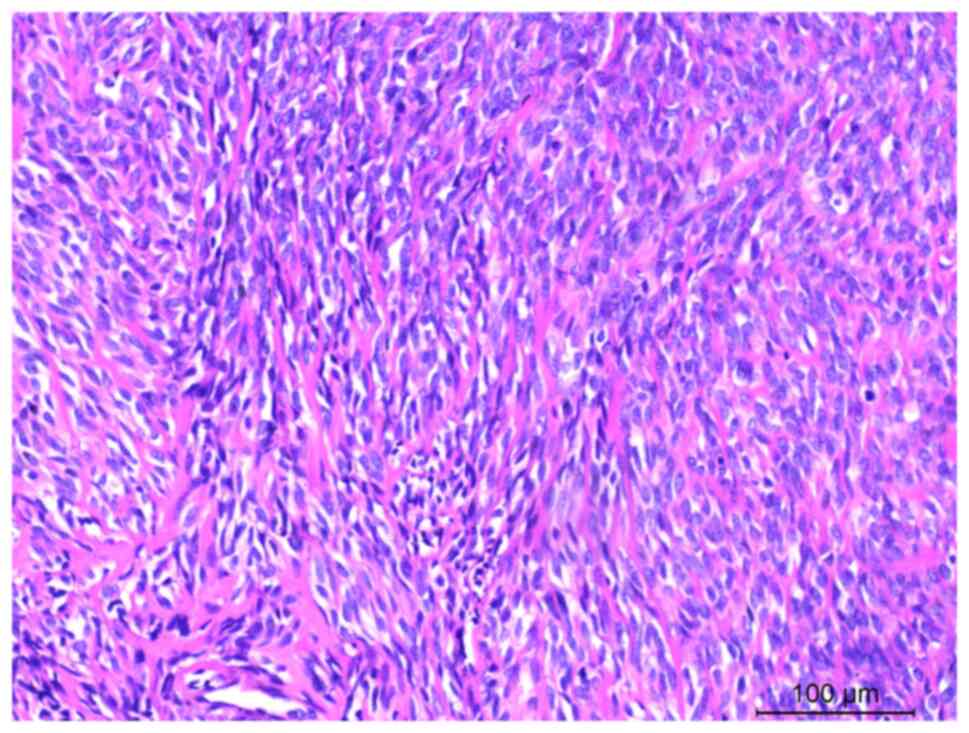

Figure 2.

Hematoxylin and eosin staining showing that the tumor is primarily comprised of spindle cells arranged in bundles, with deep-stained nuclei, inconspicuous nucleoli and abundant eosinophilic cytoplasm. Scale bar, 100 µm.

The pathological findings were of a mass of gray-white and gray-red fragmented tissue measuring 25.0×20.0×8.0 cm, with some well-defined areas. The cut surface had a fish meat-like appearance, gray-white and gray-red in color, with a solid and soft texture. The specimens were fixed in 4% neutral formalin at room temperature for 12 h, followed by routine dehydration, paraffin embedding and sectioning at a thickness of 5 µm. Hematoxylin and eosin staining was then performed at room temperature for 5 min each. Examination under a light microscopic examination revealed an incomplete tumor capsule with infiltrative growth, and tumor cells were observed to invade the surrounding muscle and adipose tissue. The tumor predominantly consisted of long spindle cells arranged in bundles, featuring darkly stained nuclei, inconspicuous nucleoli, mitosis and eosinophilic cytoplasm (Fig. 2). In a few regions, the tumor cells were naive, stellate or irregularly shaped, with interstitial mucinous edema-like changes. Some tumor cells showed lamellar necrosis and calcification (Fig. 3).

The clinical presentation of primary thoracic SCRM lacks specificity. The severity of symptoms depends on primary site and size of the tumor, the degree of compression and infiltration, and the extent of tissue destruction caused by the tumor cells. A preoperative diagnosis of SCRM is challenging due to the non-specific nature of imaging findings (2,11,12). In the present case report, the patient primarily presented with chest pain, without additional symptoms such as hemoptysis or a cough. Microscopically, the tumor predominantly consisted of spindle cells arranged in interlacing bundles, resembling fibrosarcoma and leiomyosarcoma. The spindle cells exhibited abundant red-stained cytoplasm, oval or elongated nuclei with deep staining, and inconspicuous or small nucleoli. Additionally, a small number of spindle or polygonal rhabdomyoblasts were interspersed among the spindle cells. The presence of rhabdomyoblasts suggested a diagnosis of SCRM, with mitotic figures ranging from 1 to 30 per 10 high-power fields. Immunohistochemical staining demonstrated varying degrees of expression of myogenic markers, including desmin and MyoD1, in the SCRM (13), with strong positivity for MyoD1. However, epithelial markers (such as CK and EMA) and neurogenic markers (such as S-100 and SOX-10) were not expressed.